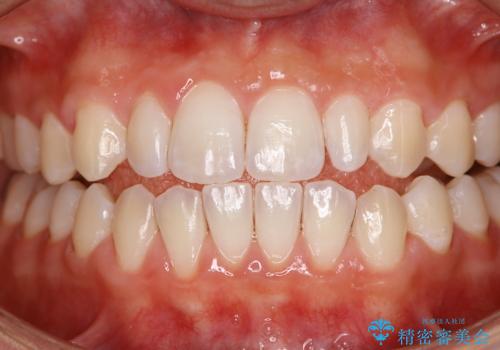

前歯が痛い!|歯の色が気になる!|精密根管治療後、オールセラミッククラウンで審美修復